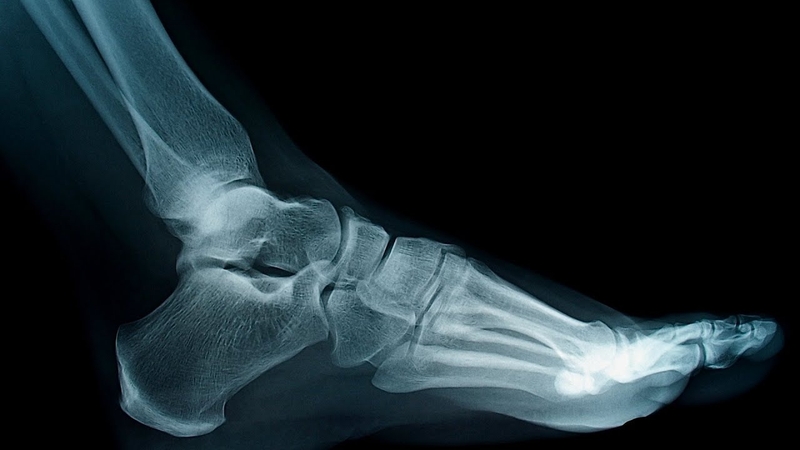

Rạn xương bàn chân có nguy hiểm không? -1

Cấu trúc xương bàn chân chi tiết gồm nhiều phần

Phương pháp chẩn đoán rạn xương

Chẩn đoán rạn xương bàn chân thường bắt đầu bằng một cuộc thăm khám cẩn thận từ bác sĩ hoặc chuyên gia y tế. Dưới đây là các phương pháp chẩn đoán thông thường được sử dụng:

• Thăm khám lâm sàng: Bác sĩ sẽ tiến hành một cuộc thăm khám kỹ lưỡng để kiểm tra vùng bàn chân bị tổn thương. Điều này bao gồm kiểm tra các triệu chứng, vị trí đau, sưng và mức độ di động của bàn chân.

• Hình ảnh chẩn đoán: Các hình ảnh chẩn đoán như tia X, CT scan hoặc MRI thường được sử dụng để xác định chính xác vị trí và mức độ của rạn xương. Tia X thường là phương pháp chẩn đoán phổ biến đầu tiên, cho phép bác sĩ nhìn thấy nếu có sự gãy hoặc nứt trong xương. CT scan cung cấp hình ảnh chi tiết hơn về xương và các cấu trúc xung quanh. MRI có thể được sử dụng để đánh giá các tổn thương mềm mà không thể nhìn thấy trên tia X.

• Kiểm tra chức năng: Trong một số trường hợp, các kiểm tra chức năng như kiểm tra sự linh hoạt và khả năng đặt trọng lượng lên bàn chân cũng có thể được thực hiện để đánh giá mức độ tổn thương và ảnh hưởng đến hoạt động hàng ngày của bệnh nhân.

Dựa trên kết quả của các phương pháp chẩn đoán này, bác sĩ sẽ đưa ra đánh giá và lên kế hoạch điều trị phù hợp nhất cho bệnh nhân.

Rạn xương bàn chân có nguy hiểm không?-3

Các cách chẩn đoán rạn xương bàn chân chính xác